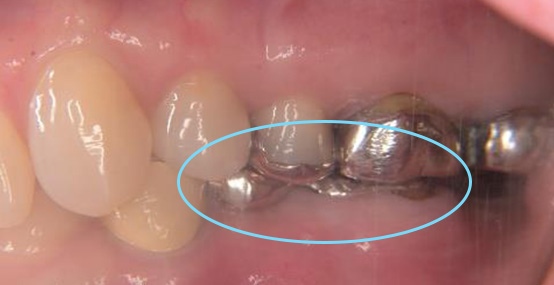

患者さまは「奥歯の被せものが外れたが、痛みがなかったのでそのままにしていた」とのことで来院されました。

検査を行ったところ、むし歯が進行しており、残念ながら歯を残すことが難しい状態でした。

奥歯を失った場合の治療方法として

をご説明しました。

ブリッジの場合は両隣の健康な歯を削る必要があること、

部分入れ歯は咬みにくさや違和感が出ることがある点などをお伝えしました。

患者さまと相談した結果、健康な歯をできるだけ守りたい、しっかり咬める歯にしたい

という理由から、インプラント治療を選択されました。

術前の状態